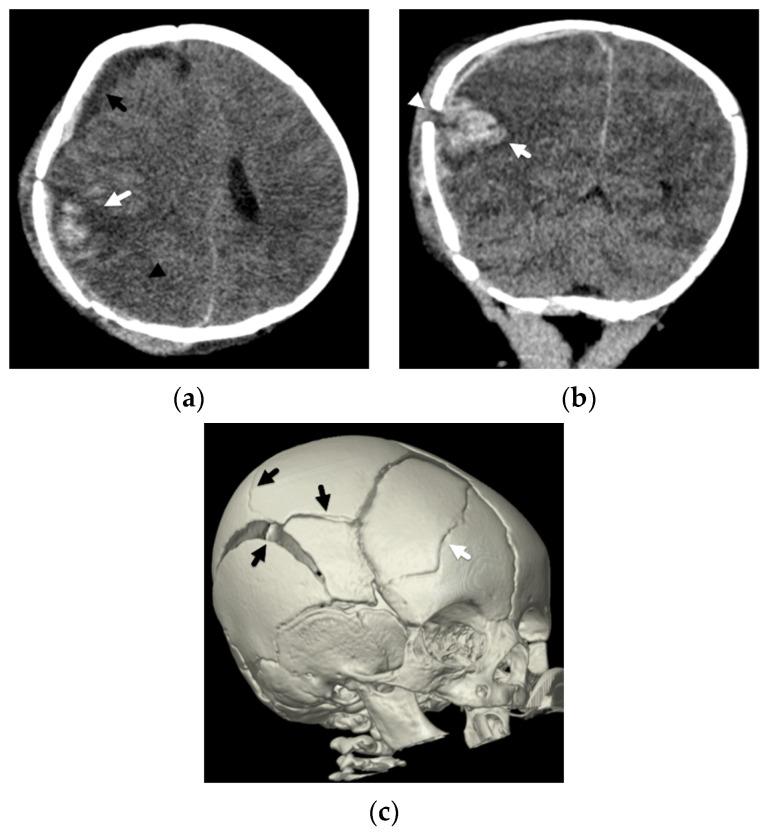

Subdural hemorrhage is a key imaging finding in cases of abusive head trauma and one that many radiologists and radiology trainees become familiar with during their years of training. Although it may prove to be a marker of trauma in a young child or infant that presents without a history of injury, the parenchymal insults in these young patients more often lead to the debilitating and sometimes devastating outcomes observed in this young population. It is important to recognize these patterns of parenchymal injuries and how they may differ from the imaging findings in other cases of traumatic injury in young children. In addition, these parenchymal insults may serve as another significant, distinguishing feature when making the medical diagnosis of abusive head injury while still considering alternative diagnoses, including accidental injury. Therefore, as radiologists, we must strive to look beyond the potential cranial injury or subdural hemorrhage for the sometimes more subtle but significant parenchymal insults in abuse.

硬膜下出血是虐待性头部创伤病例中的一项关键影像学表现,许多放射科医生和放射科实习生在多年培训过程中都对其有所了解。虽然在没有受伤史的幼儿或婴儿中,硬膜下出血可能被证明是创伤的一个标志,但这些年轻患者的脑实质损伤更常导致在这一年轻人群中观察到的使人衰弱甚至有时是毁灭性的后果。认识这些脑实质损伤的模式以及它们与幼儿其他创伤性损伤病例的影像学表现有何不同很重要。此外,在做出虐待性头部损伤的医学诊断时,在仍考虑包括意外伤害在内的其他诊断时,这些脑实质损伤可能是另一个重要的、有区别性的特征。因此,作为放射科医生,我们必须努力超越潜在的颅脑损伤或硬膜下出血,去寻找虐待中有时更细微但却很重要的脑实质损伤。